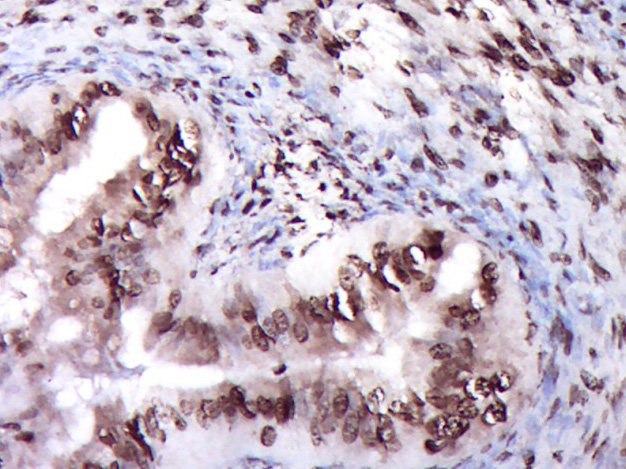

Paraformaldehyde-fixed, paraffin embedded (Mouse placenta); Antigen retrieval by boiling in sodium citrate buffer (pH6.0) for 15min; Block endogenous peroxidase by 3% hydrogen peroxide for 20 minutes; Blocking buffer (normal goat serum) at 37°C for 30min; Antibody incubation with (ZNF22) Polyclonal Antibody, Unconjugated (bs-12803R) at 1:400 overnight at 4°C, followed by operating according to SP Kit(Rabbit) (sp-0023) instructions and DAB staining.

Paraformaldehyde-fixed, paraffin embedded (Rat ovary); Antigen retrieval by boiling in sodium citrate buffer (pH6.0) for 15min; Block endogenous peroxidase by 3% hydrogen peroxide for 20 minutes; Blocking buffer (normal goat serum) at 37°C for 30min; Antibody incubation with (ZNF22) Polyclonal Antibody, Unconjugated (bs-12803R) at 1:400 overnight at 4°C, followed by operating according to SP Kit(Rabbit) (sp-0023) instructions and DAB staining.